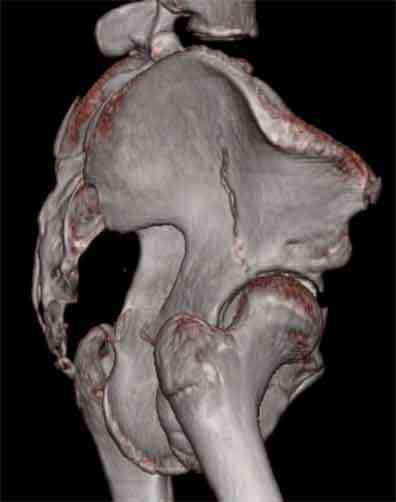

Не смог разглядеть на представленных картинках частичное повреждение левого КП, повреждение Денис1-2 справа? 3Д реконструкции в инлет и боковой проекциях убедительно не демонстрируют типа повреждения задних отделов тазового кольца(справа боковая масса скомпремирована), Наверное, у тебя есть возможность оценить тип перелома крестца по прямой проекции 3Д.

По вертлуге- смог разглядеть только изолированный перелом передней колонны.

Насколько я понял из твоего письма, обращенного к анонимному vit, ты не видишь показаний к реконструкции перелома. Я бы взялся за реконструкцию(илео-ингвинальный доступ), хоть прошел и месяц после травмы: боковая 3Д показывает смещение нагрузочной зоны впадины, что однозначно будет способствовать разрушению хряща головки и впадины( особенно у 16 летнего пациента с ожидаемым высоким уровнем активности) + изменение геометрии впадины за счет неустраненного смещения фрагментов колонны (КТ, 3Д данные).

На мой взгляд, без реконструкции этот сустав обречен (концепция вторичной конгруэтности в данных условиях работать не будет), реконструкция дает шанс на восстановление функции сустава.

Сравнивая боковые проекции 3Д реконструкций, разница переломов очевидна: в предыдущем случае на боковой проекции не видно было ступени нагрузочной зоны суставной поверхности - это и объясняет приличную функцию сустава.

Всего доброго,

Трудно классифицировать перелом ацетабулума месячной давности у молодых. Сильно развитая надкостница иногда не дает сместиться фрагментам и происходит сращение в короткие сроки.

По представленным материалам, мне кажется, перелом был передней колонны ацетабулум с минимальным вовлечением нагрузочной поверхности сустава, левосторенний повреждение КПС и лонных костей.